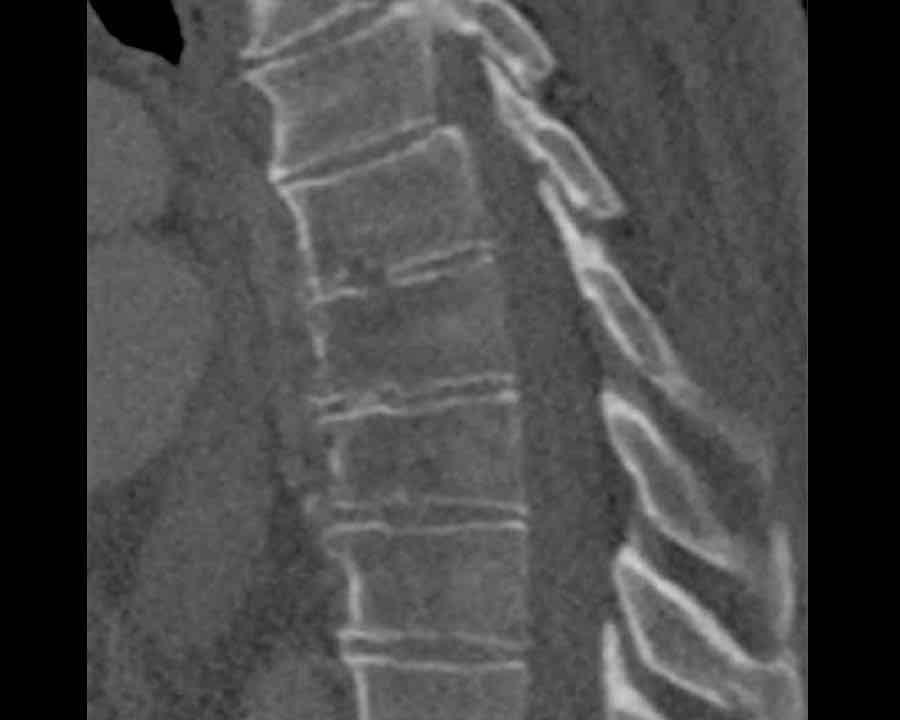

Scroll through images.

What are the findings?

Findings

- C injury? No.

- Signs of a rigid spine?

Yes (DISH), so a B3 injury is very likely. - A subtle fracture on the anterior vertebral body (arrows).

- No separation, probably due to positioning of patient in the scanner

Conclusion

Injury type B3.